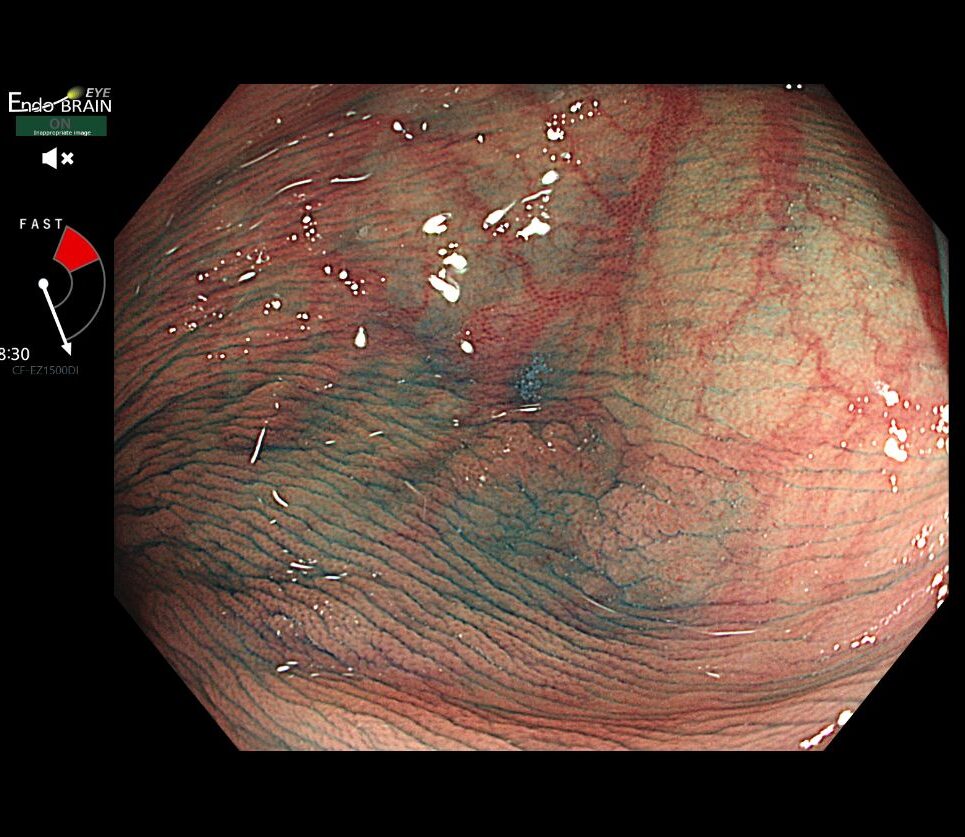

先日、大腸のなかでもヒダが鋭角で死角ができやすい「横行結腸」において、オリンパスの内視鏡画像診断支援システム「EndoBRAIN-EYE」が「正常」と判断するような、ごくわずかな変化に遭遇しました。

一見すると異常のない粘膜です。しかし、その場所に付着した「不自然な粘液(Mucus cap)」が、私には強い違和感として映りました。

通常光での観察

平坦で周囲の粘膜と色が似ており、EndoBRAIN-EYEも「正常」と判断しました。わずかな粘液の付着が唯一のサインです。